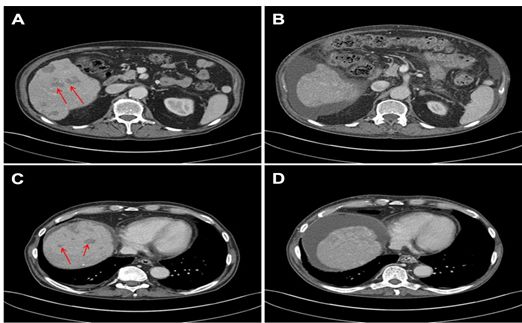

质子治疗前(A、C)和治疗后(B、D)